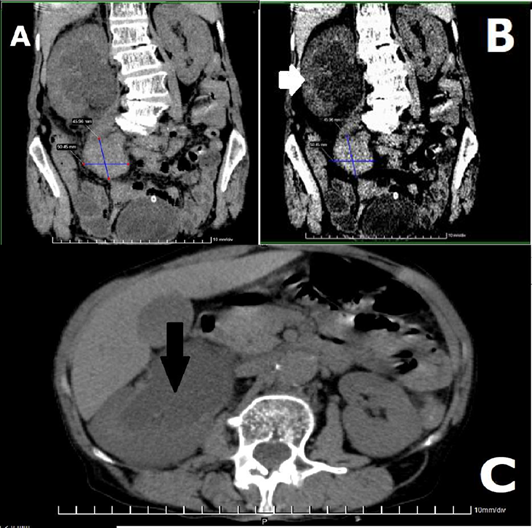

An abdominal ultrasound was performed, observing moderate right ureterohydronephrosis and aneurysmal dilatation of the right external iliac artery that compresses the right ureter and the presence of fluid around the aneurysm. A simple emergency tomography was performed due to the azotemia figures that prevented a contrast study, where ureterohydronephrosis of the right kidney due to compression of the ureter by a possibly right aneurysmal tumor (T?) was observed, coinciding with the ultrasound (Figures 1A, 1B).

A cross-sectional tomographic view shows moderate dilation of the renal cavities with preserved parenchyma (Figure 1C). An angiography was not performed due to the severity of the clinical picture that warranted referral to a higher level care center, interconsultation with the Angiology Service who performed repair of the fissured aneurysm using the conventional technique.

Figure 1 Simple Computed Axial Tomography. TO:Reconstruction with a window for the abdomen shows an aneurysm (50.45X 45.96mm) of the right iliac artery that compresses the ipsilateral ureter with secondary ureterohydronephrosis. B: Dilatation of the right upper urinary tract (white arrow) can be seen. C: Cross section showing the right renal pyelocaliectasis (black arrow).